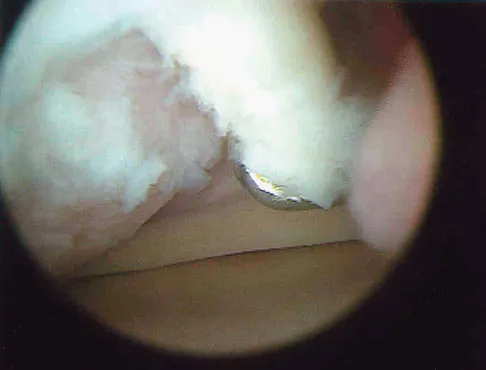

A 21-year-old soccer player reports pain and is unable to straighten his knee following an acute injury during a game. He is unable to continue to play. An MRI scan is shown in Figure 3. What is the next most appropriate step in management?

Explanation